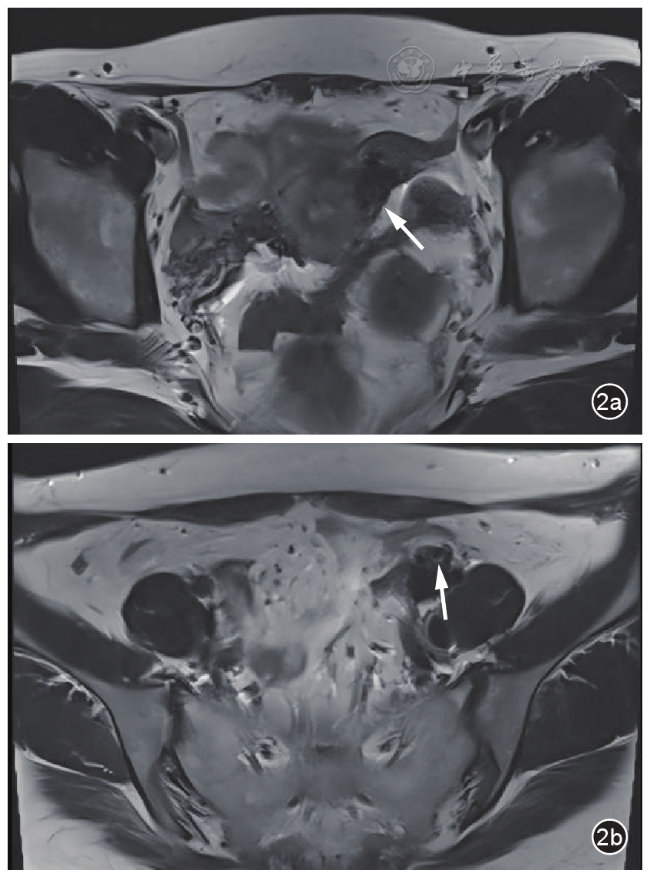

图2 盆腔静脉侵袭性葡萄胎患者化疗前盆腔MRI T2加权横断面成像。图a示子宫左侧宫旁静脉迂曲增粗,内见数个囊状结构(箭头所示);图b示左侧扩张髂静脉内见囊泡状结构(箭头所示)

入院妇科查体左附件区呈增厚感,无压痛,右附件区未见异常。经阴道超声检查显示子宫宫腔内可见支架回声,内膜菲薄,左侧壁上段临近浆膜层处肌层回声不均,局部可见团块状中高回声,大小1.4 cm×1.3 cm;左侧宫旁静脉及髂静脉显著扩张,最宽处达到1.4 cm,内部可见多个薄壁囊泡状无回声及条索状的中等回声结构,其中较大的无回声直径约为0.9 cm。动态观察显示子宫左侧壁上段临近浆膜层处中高回声与宫旁扩张静脉内异常回声相连。双侧附件区未见明确囊实性包块。彩色多普勒血流成像(color Doppler flow imaging,CDFI)显示宫旁扩张静脉及髂静脉的囊泡状无回声内未见血流信号,周边残余管腔血流充盈尚可(图1)。超声检查提示子宫肌层及左侧盆腔静脉内异常回声,结合临床考虑侵袭性葡萄胎可能。盆腔动态增强MRI显示子宫左侧壁上段可见小囊状长T2信号,邻近伴多发迂曲略粗血管流空信号;左侧附件区可见不规则小片状等T2信号及多发小囊状长T1长T2信号,强化不均,邻近宫旁静脉迂曲增粗呈蚓状,范围约4.4 cm×1.7 cm,提示左侧附件区及子宫左侧壁上段见多发异常信号及血管流空影,妊娠滋养细胞肿瘤不除外(图2)。患者胸部CT、心脏超声、心电图未见明显异常。